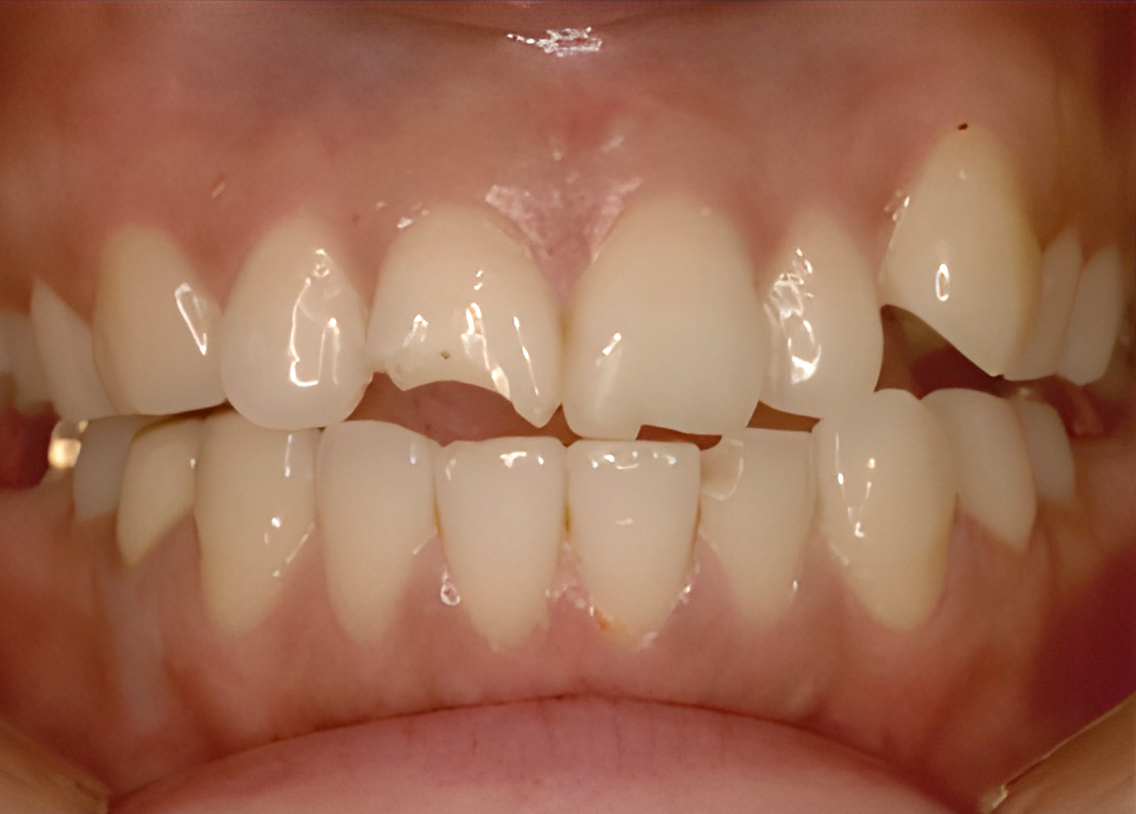

Before

after